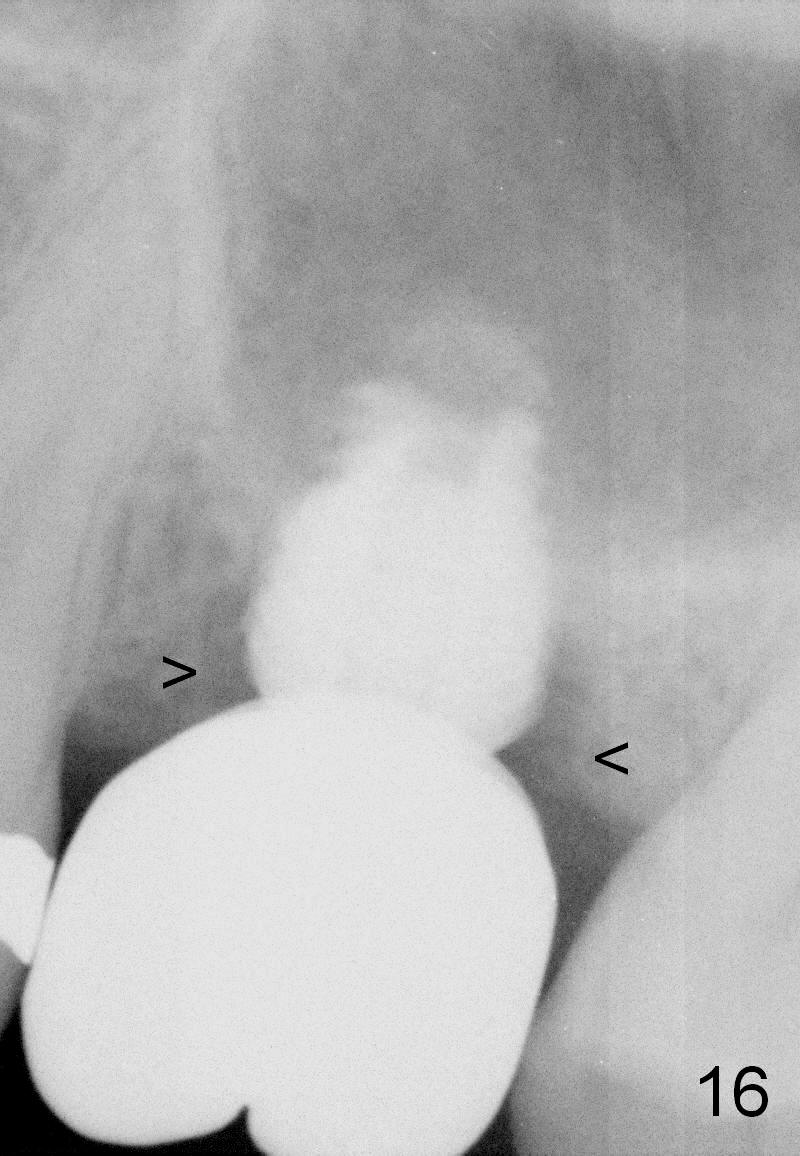

A 45-year-old man has lost the tooth #14 for a while (Fig.1); bone height is 5.4 mm. An extra wide and short implant is planned. Torus palatinus is large, suggesting that bone density should be high. A 6 mm tissue punch is chosen, but it is placed more palatal. If it were placed in the middle of the ridge, there would be no buccal keratinized gingiva (incision may avoid this issue). Additionally, the buccal portion of punch is made incomplete so that there is pedicle on the buccal side when the flap is raised (Fig.4,8: F). It is expected that the excess portion of keratinized tissue will form thick gingiva buccally. Osteotomy proves that bone is dense (Fig.2 (4.5x11 mm tap). Typical sinus lift is finished with placement of 6.4x6 mm (extra wide) bone-level implant (Fig.3, >55 Ncm). Following further torque, Fig.4 shows that the implant (I) is sub-gingival (<). Bitewings are taken to confirm that the implant plateau is at the crestal level (Fig.5,6 ^). PA shows sinus lift (Fig.7 *). The lingual aspect of the implant and healing abutment (H) is further bone grafted and covered by collagen dressing (Fig.8 *). The wound is protected with perio dressing. When the latter dislodges 7 days postop, the collagen dressing and bone graft are lost as well (Fig.10), while the buccal flap remains vital (Fig.9). The lingual exposed plateau should be able to heal normal. The collagen dressing should have been fixed in place by suture or as simple as a dental floss. There is mild nasal hemorrhage 1-2 days postop, possibly related to sinus membrane perforation and inability of Collagen Dressing to cover the perforation and contain the bone graft. When the patient returns for #9 implant placement in 3 weeks postop, the buccal flap reduces in size (Fig.11 *), while the palatal wound has healed with minimal exposure of the implant (Fig.12). Sinus graft remains in place 3 months postop (Fig.13); the buccal flap appears to have incorporated into a part of the gingiva (Fig.14). The bone density of the sinus lift appears to increase 10 days later when an abutment is placed (Fig.15 *). Although oral hygiene is pristine, there is apparent crestal bone resorption 12 months (Fig.16) and 20 months (Fig.17) post cementation, probably due to unfavorable crown/implant ratio and bruxism as well as pre-implantation bone loss (Fig.18,19). In contrast, an immediate implant in the same patient avoids pre- or post-implantation bone loss. In fact both the soft (Fig.20) and hard (Fig.21) tissues remain healthy 2 years 8 months post cementation. The sinus lift remains 3 years 8 months post cementation (Fig.22), while the crestal bone loss persists. The patients keeps complains of food impaction distal associated with bad smell 4 years 1 month post cementation. In fact the distal proximal contact is within normal limit. The bad smell is probably due to crestal bone loss (Fig.23 (pan), 24 (CT) *) and periimplantitis. Bone graft, PRF and Cytoplast membrane will be needed and fixed in place with long healing screw. When the patient returns for crown redo, he also reveals floss related gingival hemorrhage. There is pain associated with palatal sulcus probing with light gingiva erythema. Review of CT coronal section shows possible palatal (Fig.25 P) bone loss (*).